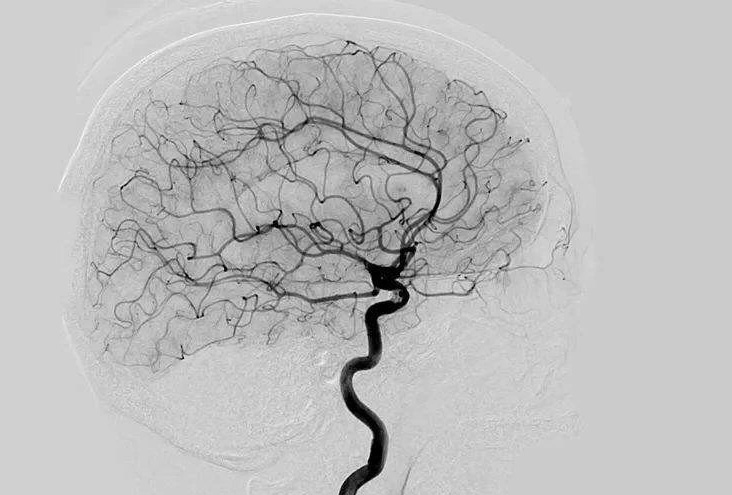

Digital Subtraction Angiography 血管造影機又稱數(shù)字減影血管造影機,是通過電子計算機進行輔助成像的血管造影方法,應用計算機程序進行兩次成像完成的。在注人造影劑之前,第一次成像工作,圖像轉(zhuǎn)成數(shù)字信號儲存,注人造影劑后,再次成像并轉(zhuǎn)換成數(shù)字信號,兩次數(shù)字相減,消除相同的信號,得到只有造影劑的血管圖像。臨床主要應用于冠心病、心律失常、瓣膜病和先天性心臟病的診斷和治療。